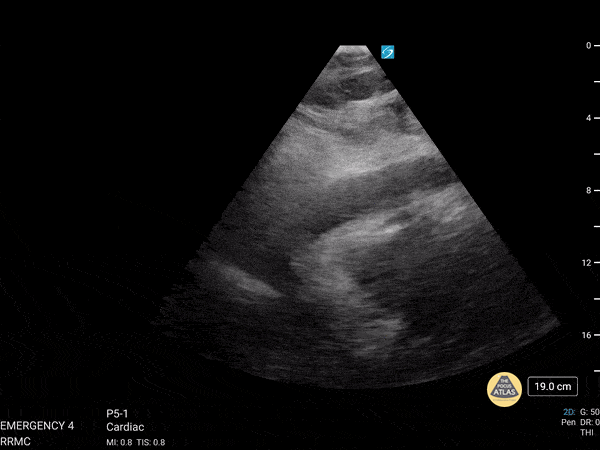

Here is an excellent of example of utilizing Rapid Ultrasound for Shock and Hypotension (RUSH). This was from a 77 year old patient who presented initially presented with progressive weakness and a fall while in the bathroom. His initial blood pressure was labile but not hypotensive. Workup revealed leukocytosis in the presence of anuria and was eventually admitted with broad spectrum antibiotics. Shortly after admission, he became increasingly hypotensive and required norepinephrine. RUSH performed initially with the intention of assessing IVC for fluid status however the image above was discovered. There is obvious right ventricular diastolic collapse in the presence of pericardial effusion, consistent with cardiac tamponade. Dr. Austin Shanks, MD, PGY-2 Riverside Regional Medical Center Emergency Medicine Residency (Newport News, VA)